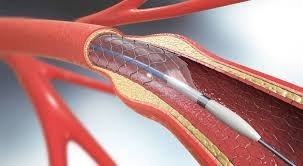

A specialized procedure used to diagnose and treat disorders of the bile ducts and pancreas. Common indications include: